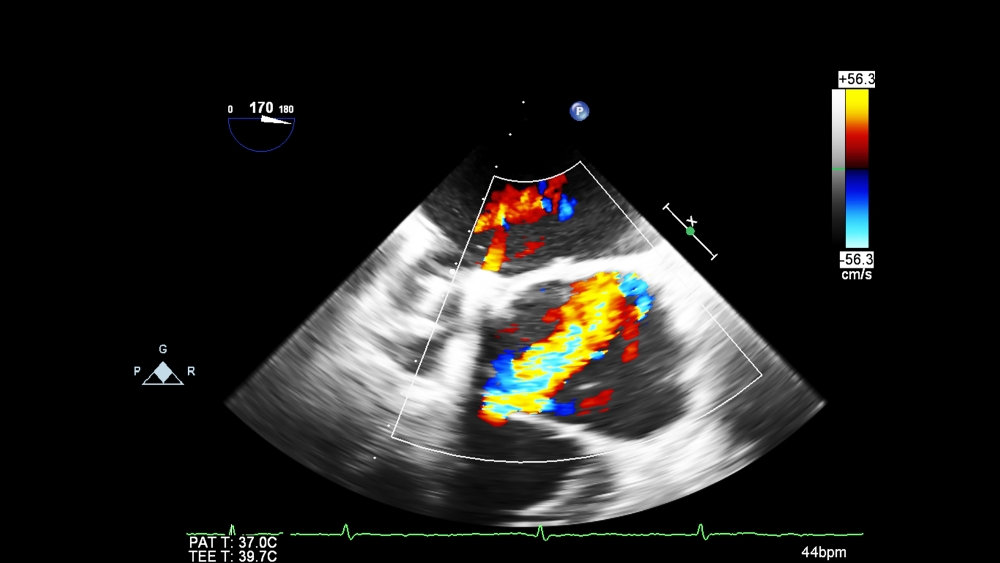

transesophageal ultrasound with Doppler mode

3. During the procedure, your doctor will use an echotransducer, a device that produces high-frequency sound waves, and place it down your food pipe (esophagus) to look closely at your heart valves and chambers to check for abnormalities.